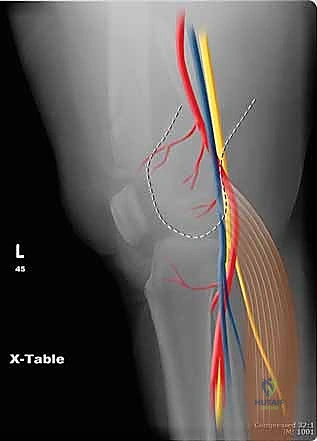

لفهم مدى تعقيد هذه الكسور، يجب أن نغوص في التشريح الدقيق لهذه المنطقة. يمثل الجزء السفلي من عظم الفخذ نقطة الارتكاز الأساسية لوزن الجسم أثناء الحركة والوقوف.

يمر المحور الميكانيكي لعظم الفخذ من مركز رأس عظم الفخذ إلى مركز الركبة، وعادة ما ينحرف بمقدار 3 درجات عن الخط العمودي. يستمر هذا المحور بعد ذلك إلى مركز الكاحل، ليحدد المحور الميكانيكي للطرف بأكمله. في المقابل، يظهر المحور التشريحي لعظم الفخذ مع حوالي 9 درجات من الانحراف الخارجي (Valgus) بالنسبة لمحور مفصل الركبة.

- الأشعة السينية (X-Rays): أخذ صور من زوايا متعددة (أمامي خلفي، وجانبي) لتحديد موقع الكسر ونوعه.

قبل بدء الجراحة، يتم رسم خطة دقيقة. يتم وضع المريض على طاولة العمليات المجهزة بأشعة (C-Arm) لضمان التصوير الفوري أثناء الجراحة.

يستخدم الدكتور هطيف تقنيات الفتح الجراحي المحدود (Minimally Invasive Plate Osteosynthesis - MIPO) كلما أمكن ذلك، للحفاظ على التروية الدموية للعظم وتسريع الالتئام. يتم عمل شق جانبي بعناية للوصول إلى منطقة الكسر دون الإضرار بالعضلات المحيطة.

- الجراحة الميكروسكوبية: للتعامل مع الأعصاب والأوعية الدموية الدقيقة المحيطة بالركبة.